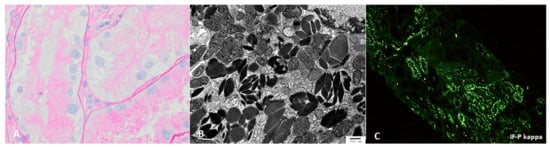

Light chain proximal tubulopathy (LCPT) has crystalline or non-crystalline inclusions of monoclonal light chains in proximal tubules with associated tubular injury; similar crystalline paraprotein inclusions can be identified in other kidney cells, including podocytes [57,58] and histiocytes [4,59,60] (Figure 2).

Like other proteins, these are physiologically reabsorbed via the megalin/cubulin pathway in proximal tubules, but properties of the variable (V) region in particular confer increased resistance to proteolysis or degradation by lysosomal enzymes, and propensity for crystal formation [4,5,6]. This intercellular accumulation of monoclonal free light causes increased oxidative stress and apoptosis [2]. The majority of crystalline LCPT is kappa light chain, and non-crystalline LCPT is generally lambda light chain [4,53]. IF-P is substantially more sensitive than IF-F for identifying crystalline LCPT [4]; since light microscopic findings may also be subtle, electron microscopy and IF-P can be critical for identifying LCPT [53,61]. In approximately 75% of patients with LCPT, diagnosis on renal biopsy represents the initial identification of a lymphoproliferative disorder [4,53].